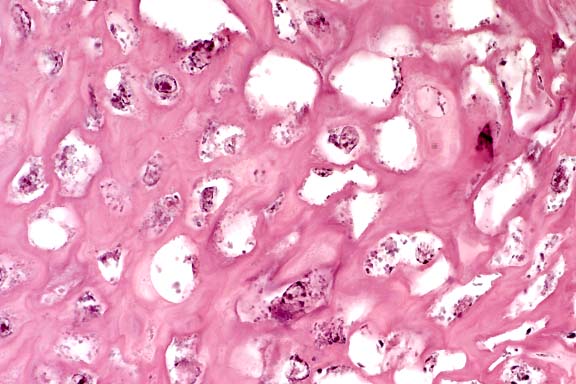

- Case 4-2. Kidney. There is multifocal liquefactive

necrosis of medullary collecting tubules characterized by an

infiltrate of neutrophils, histiocytes, and occasional faint

5-10µ yeasts.

40x

Obj.

- Case 4-2. Kidney. Lumena of necrotic collecting tubules

are filled with pale fungal hyphae and surrounded by neutrophils

and fewer macrophages.

- AFIP Diagnosis: Kidney: Nephritis, necrosuppurative,

multifocally extensive, severe, with necrotizing vasculitis and

numerous fungal hyphae, German Shepherd Dog, canine, etiology

consistent with Aspergillus sp.